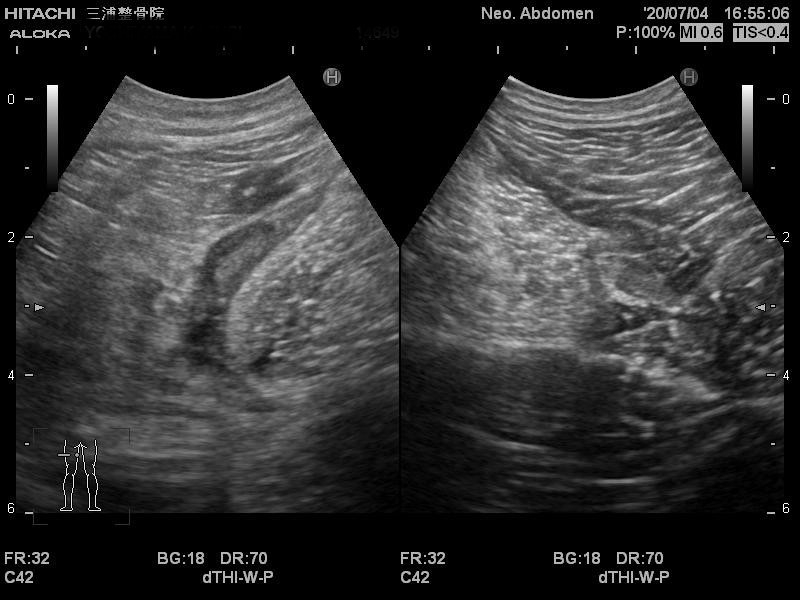

エコーではこのように写ります。

患側では大きく腫れて

正常な靭帯線維が見えないため

二分靭帯が断裂しています。